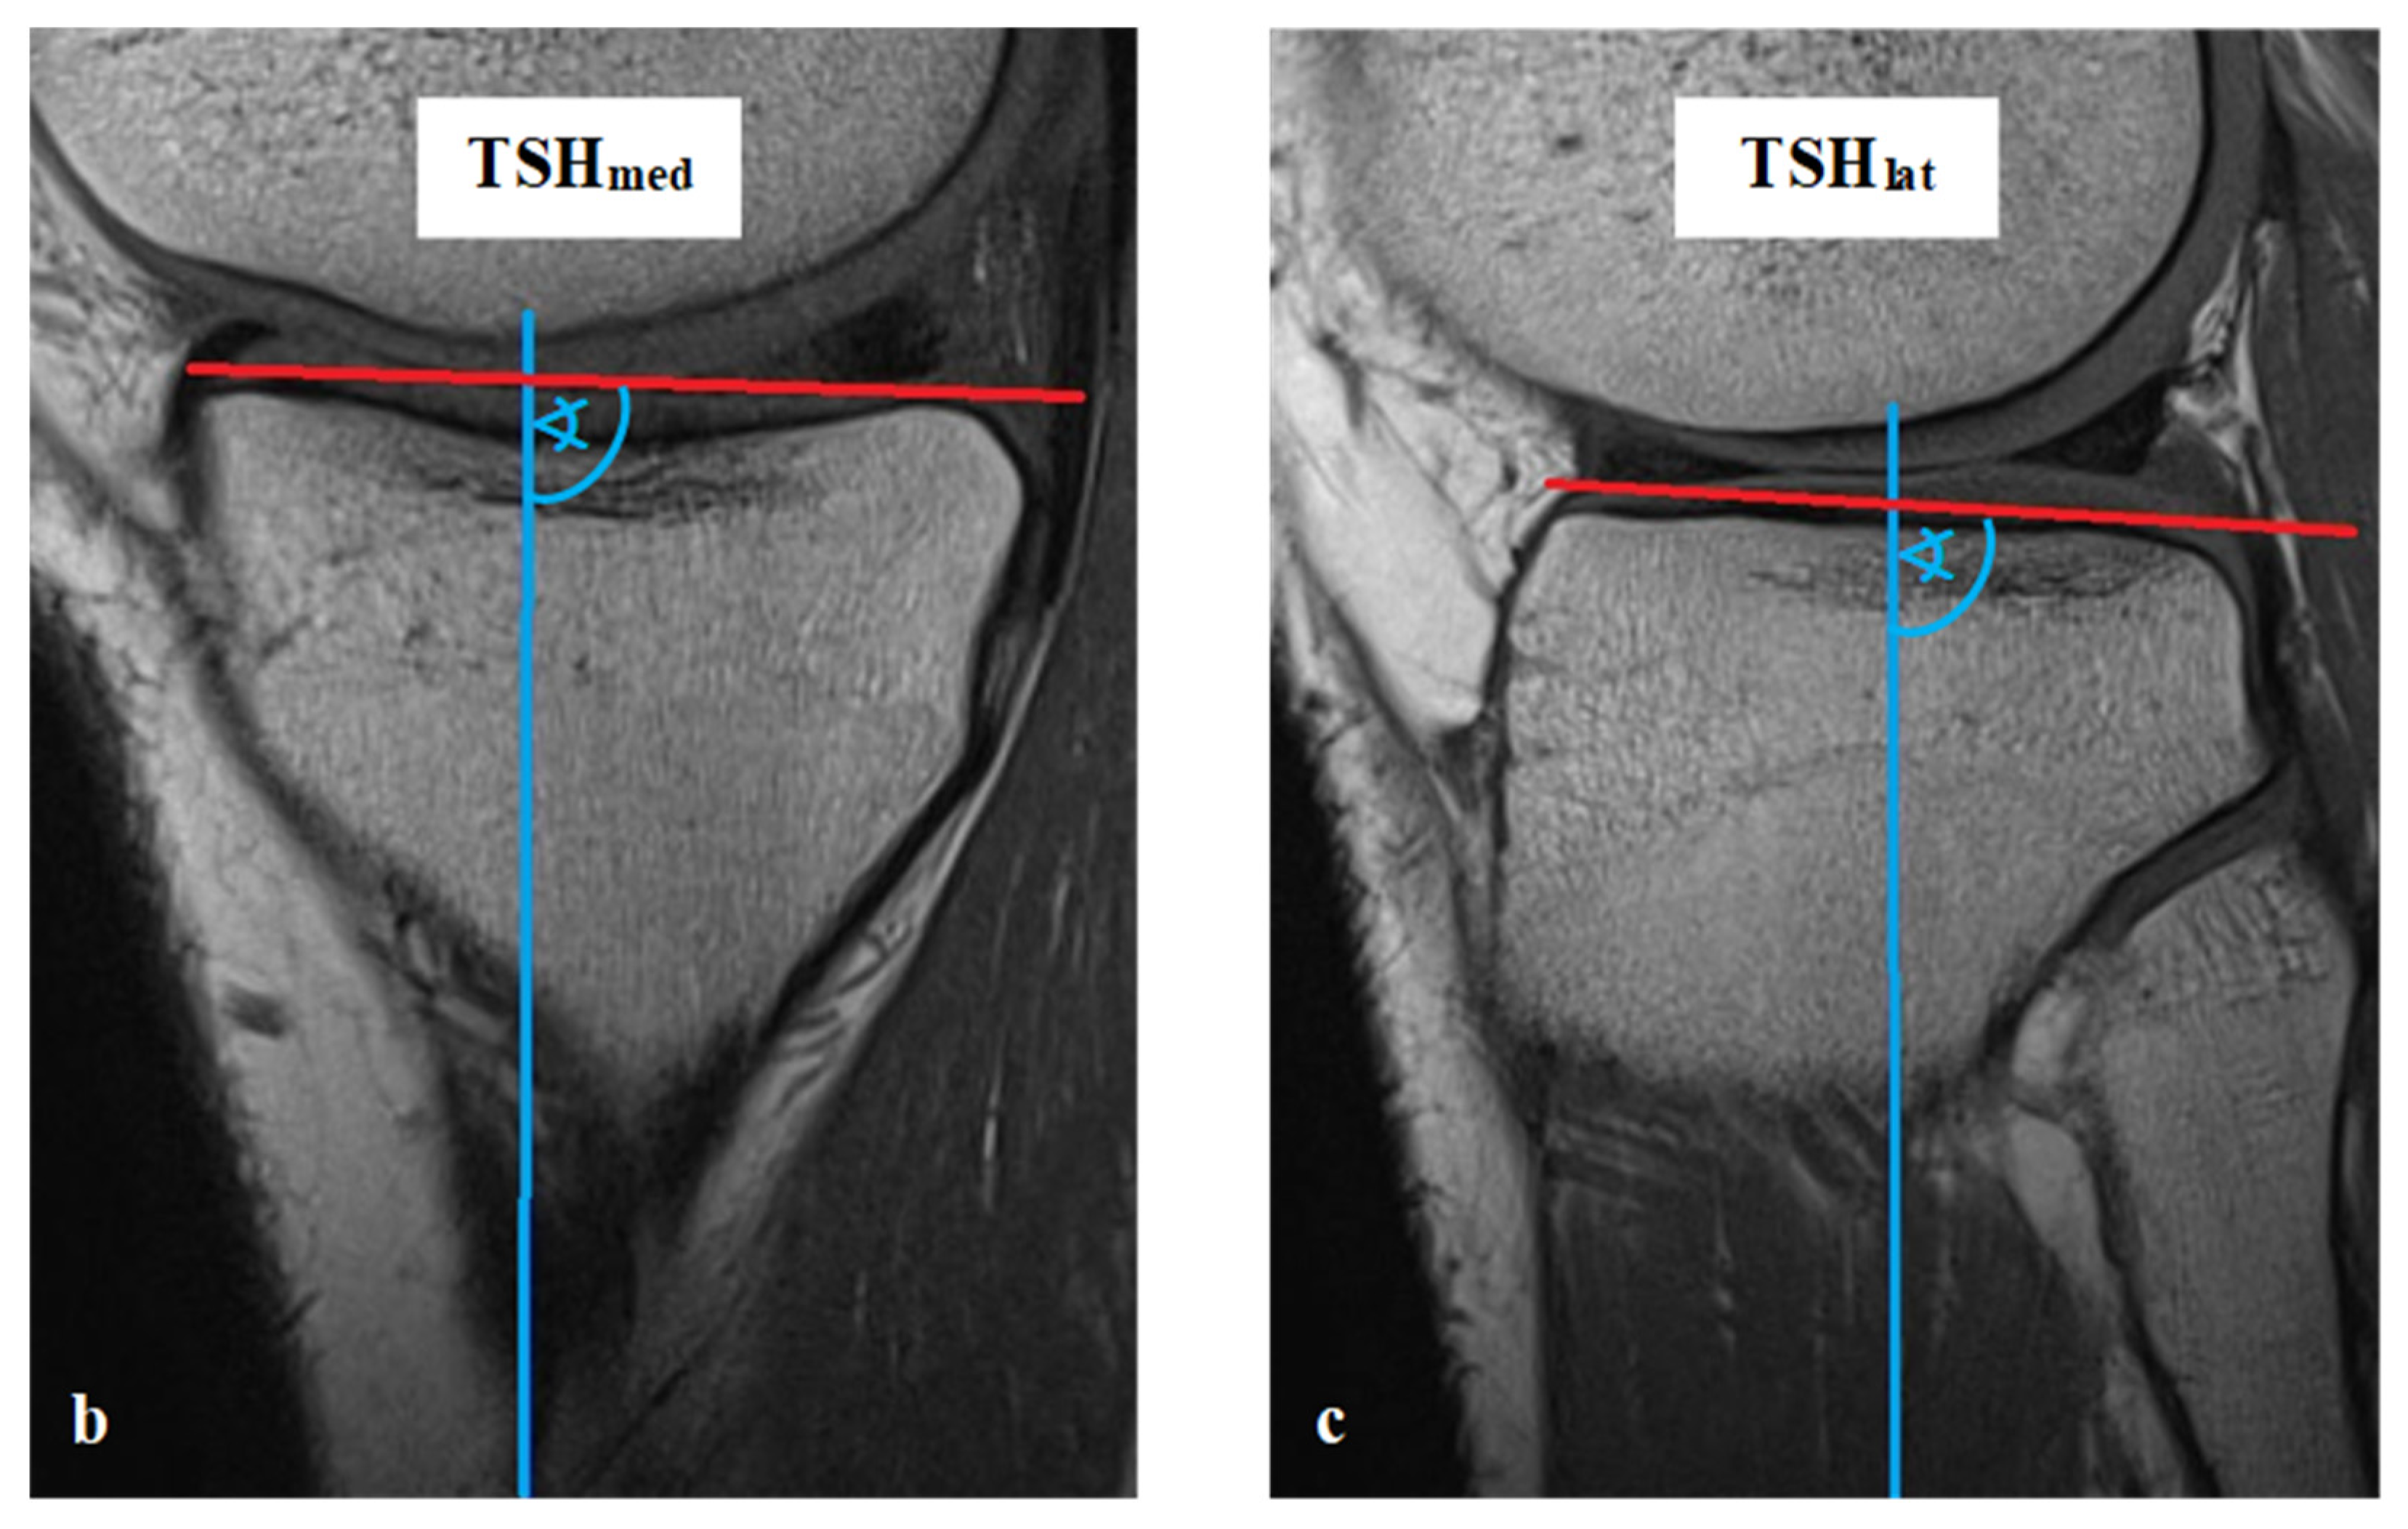

All measurements were taken via the PACS system (Picture Archiving and Communication System). Software from GE Healthcare called CentricityTM Universal Viewer was used (RA1000, edition 2019, Buckinghamshire, Great Britain). The osteoarthritis score of each knee joint was classified according to Kellgren/Lawrence (KL), in order to group patients as KJH or KJD. The TS was measured on the medial and lateral knee-joint surface according to Karimi et al. (TSKmed and TSKlat) [37] and Hudek et al. (TSHmed and TSHlat) [38]. As a reference for determining the inclination of the tibial plateau, Karimi et al. described the dorsal tibial bone cortex and Hudek et al. the tibial-shaft axis. Figure 1 and Figure 2 show the principle of the measurement methodology.

Figure 2.

Exemplary depiction of the measurements of the tibial slope according to Hudek et al. [38] for medial (TSHmed, (b)) and lateral (TSHlat, (c)) knee-joint surface: The measurements of TSH were performed in sagittal view of the knee joint in MRIs. To determine the right position of tibial-shaft axis for each TSHmed and TSHlat, a reference line was set in the best available image. To detect the tibial-shaft axis as accurate as possible, two virtual circle stencils were used (a). The reference structures were the posterior cruciate ligament (PCL) and the intercondyloid eminence (IE). Based on this reference line, the inclination angle of the tibial plateau was determined in the medial (TSHmed, (b)) and lateral (TSHlat, (c)) joint sections.